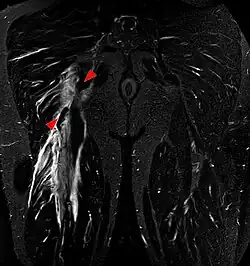

Klinische Bedeutung

Ein Einriss oder Abriss eines Teils oder der ganzen ischiocruralen Muskulatur ist eine häufige Verletzung, die oft bei Sportarten mit plötzlichen, abrupten Bewegungen wie z. B. Wasserski oder Fußball auftritt. Die Behandlung kann operativ oder konservativ erfolgen, wobei sich die Entscheidung für den einen oder anderen Weg auch nach dem Ausmaß der Verletzung (kompletter Riss oder nur ein Teil) richtet.[4][5]